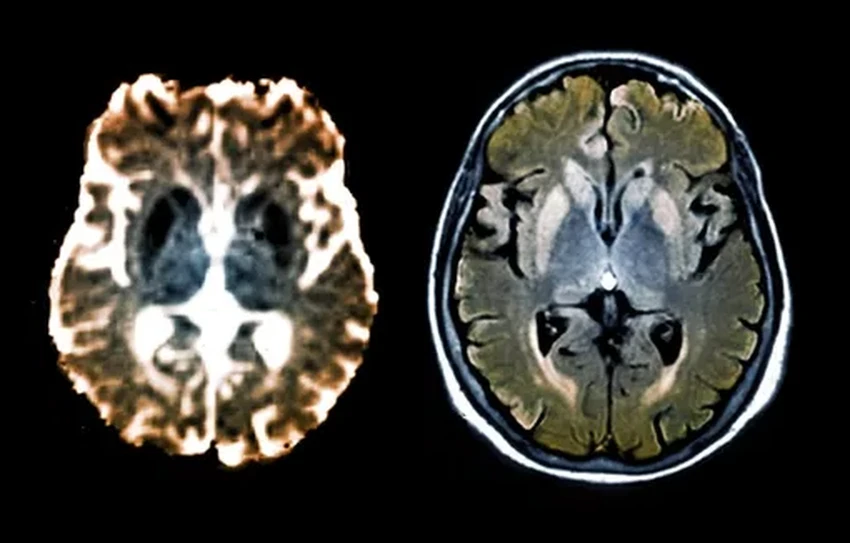

Альцгеймер, Паркинсон, прионные болезни… Объединяет их жуткая поломка на молекулярном уровне: гены начинают штамповать бракованные белки, которые засоряют и уничтожают нейроны. Менять сам геном — дело рискованное. Но природа, оказывается, давно придумала изящный обходной путь — эпигенетическое редактирование. Можно просто «заглушить» проблемный ген, не трогая его код. Ученые взяли на вооружение этот природный механизм и применили «редактор эпигенома» к генам, производящим смертельные прионы. Эксперимент на мышах увенчался успехом: производство ядовитых белков остановилось. Звучит как начало новой эры в неврологии, не правда ли?

Как вы находите дорогу в полной темноте? Ваш гиппокамп — вот кто настоящий герой. Нейроны в этой зоне мозга рисуют детальные когнитивные карты, и раньше мы думали, что для этого им нужны визуальные ориентиры. Новые исследования ломают этот стереотип: оказывается, мозг умудряется настраивать свою GPS-систему даже вслепую, используя другие сигналы. Понимание этих механизмов — это не просто фундаментальная наука. Это ключ к лечению болезней, стирающих память и пространственную ориентацию, и золотая жила для робототехников, мечтающих создать по-настоящему автономные машины.